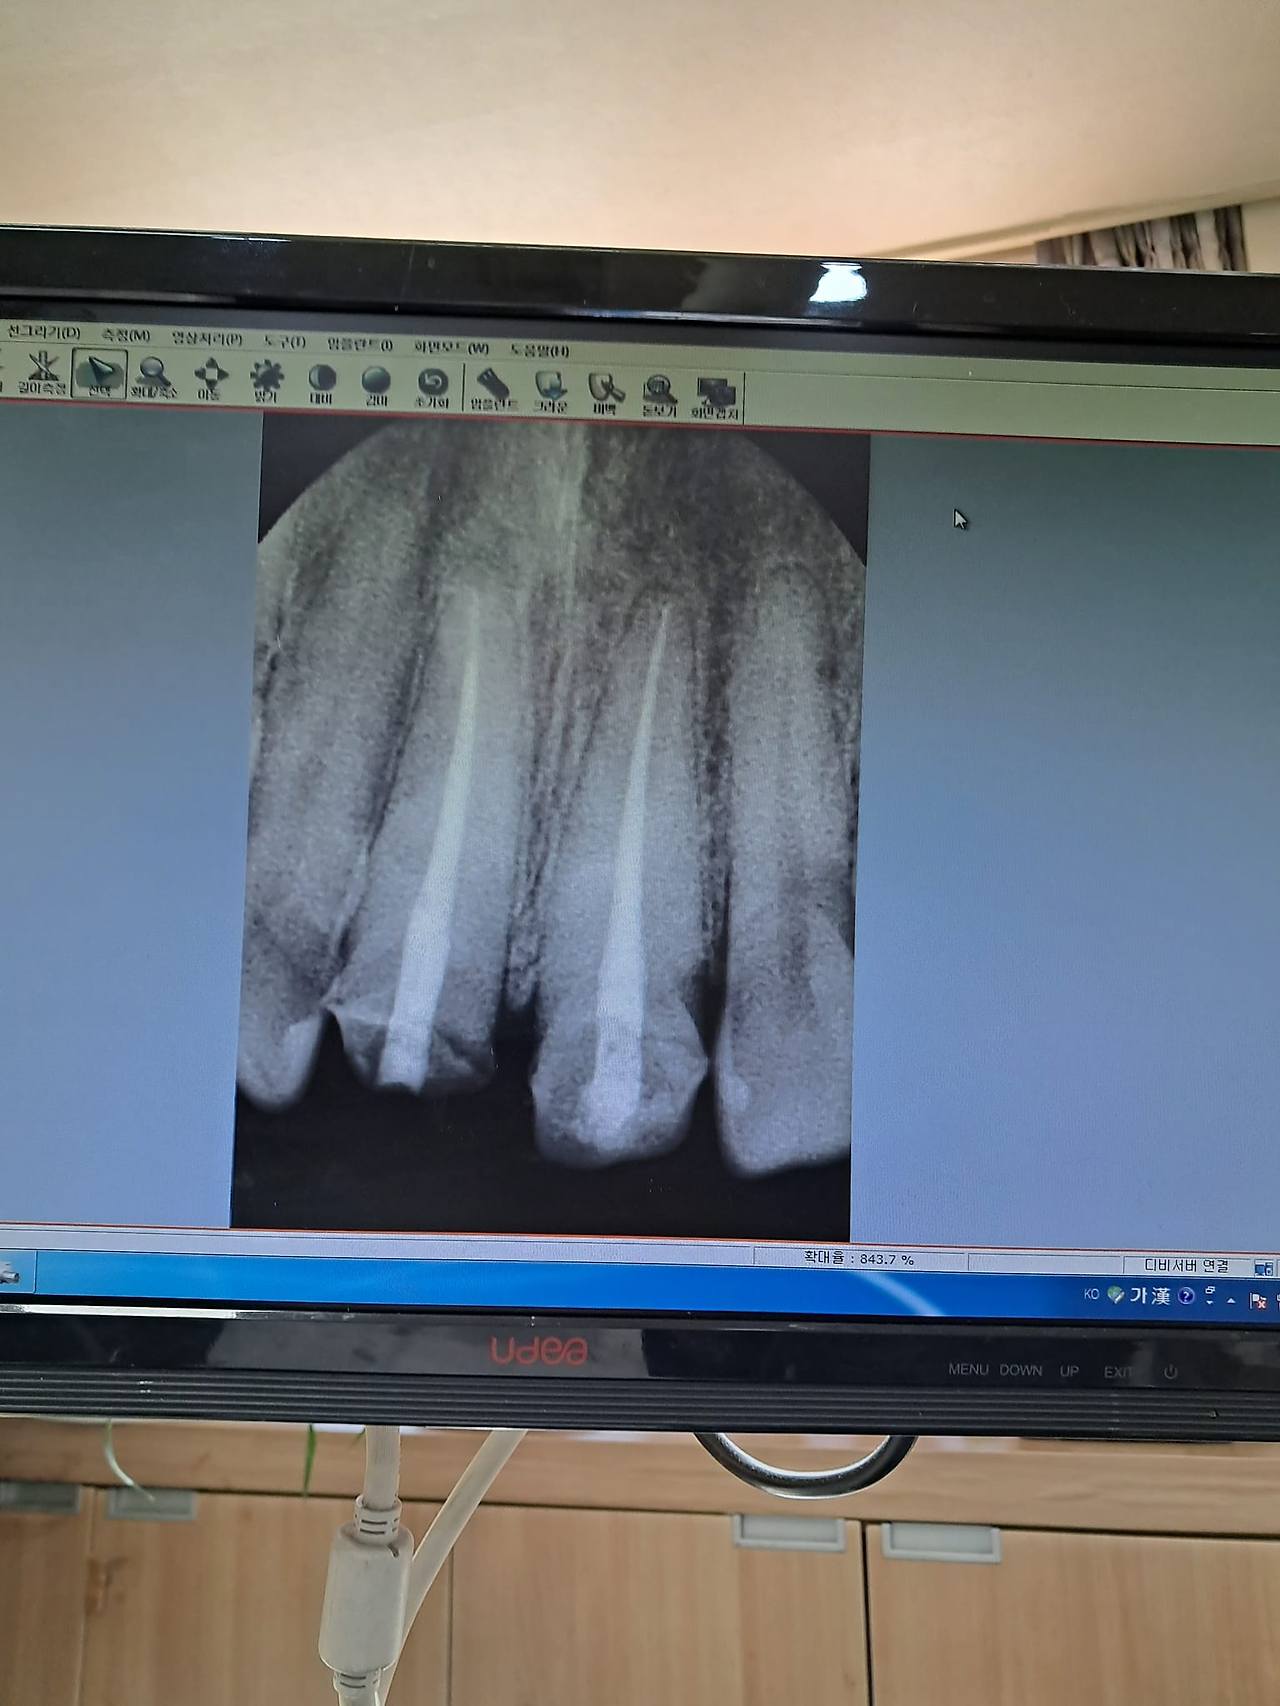

4. 마지막으로 정말 울고 싶은 게 있는데 치과 ㅅㅂ ㅠㅠ

임플란트를 안 하는 대신 부러진 앞니 만큼 치아 뿌리를 교정으로 끌어당겨 아래로 내리게 한 다음 크라운 씌우는 작업을 거의 반년에 걸쳐 하기로 결정했다.

일단 내 치아를 쓰도록 가이드 했다는 점에서 +100점이지만 나는 앞으로 3-4개월을 앞니 6개에 교정기를 부착한 영구(그래, 심형래의 영구없다! 바로 그 영구가 맞다)로 살아야 한다!

템포러리라고 불리우는 임시치아가 치아뿌리를 끌어내리는 데 방해가 되기 때문에 앞니의 70%는 빈공간인 영구 상태로 살아야 한다. 섹시캐에서 개그캐로 거듭났다.

그래서 첫번째 병원에서는 임플란트까진 아니었지만 심하게 훼손된 오른쪽 치아부리에 지지대를 세우고 크라운을 씌우자 했었다. 하지만 여러 의사가 협력하는 병원에서는 남은 치아뼈로 교정을 한 다음 보철을 하는 완전히 새로운 솔루션을 주셨다.

쏘카반납 전 박살남 후방 찍어 봄.jpg / 박살난치아xray.jpg